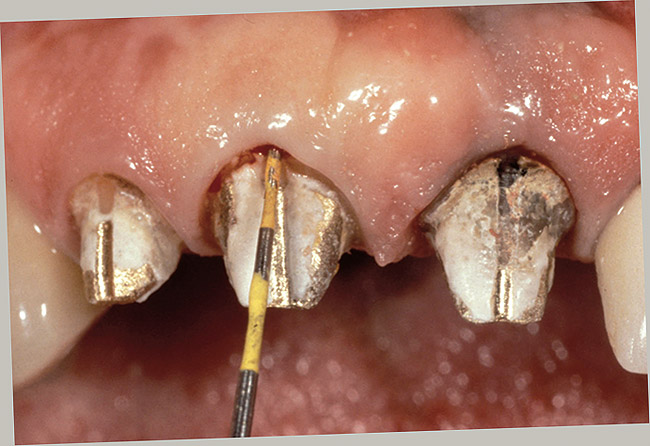

Clinical Procedures in Margin Placement

The placement of supragingival or equigingival margins is simple because they require no tissue manipulation. Regarding overall tooth preparation, the amount reduced incisally or occlusally, facially, lingually, and interproximally will be dictated by the choice of restorative materials. Before extending subgingivally, prepare every tooth right to the free gingival margin facially and interproximally. This allows the margin of the tooth preparation to be used asa reference for subgingival extension once the tissue is retracted (Figures 13, Figure 14, Figure 15 and Figure 16).

Figure 1  View of 4 porcelain veneer preparations with the margins placed at the level of tissue.

Figure 1

Figure 16  The first step in controlling margin placement is to prepare the tooth even with the gingival margin.

Figure 16